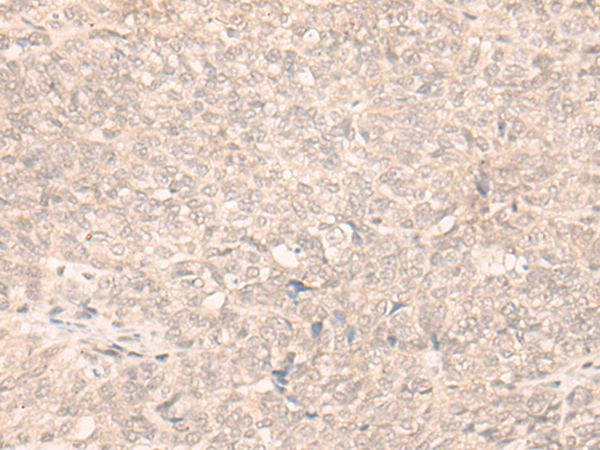

ELISA, IHC

IHC positive control:

Human lung cancer and Human ovarian cancer

IHC Recommend dilution:

30-150